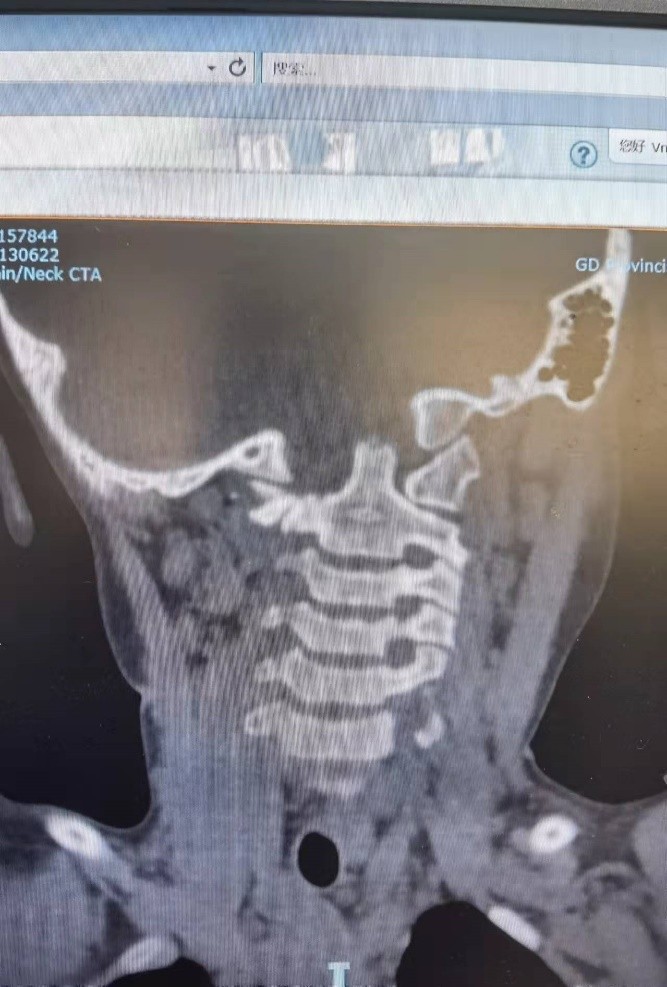

检查显示严重的寰枢椎固定脱位,脊髓也受到压迫。

牵引复位,螺钉固定,植骨融合,效果还是非常好。我们的手术安全并且出血极少。